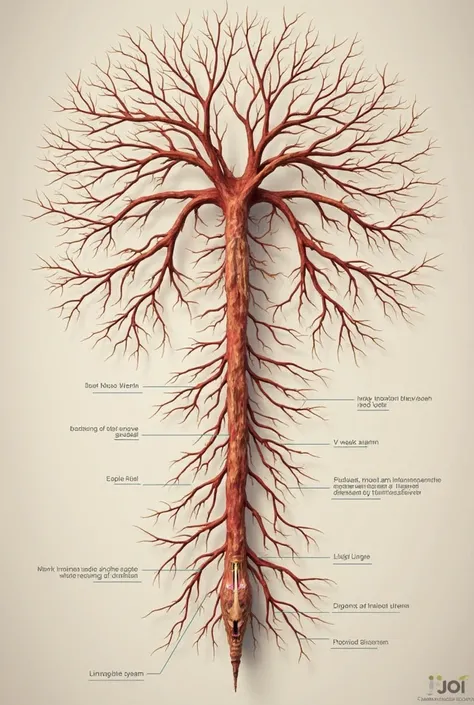

A diagram of the anatomy of the human body

Realice un dibujo de la piel. Coloque las siguientes referencias: Epidermis Fermis Hypodermis Keratinized squamous stratified epithelium Hair Sebaceous gland Sweat gland Pilo erector muscle Connective tissue Blood vessels Nerves Adipocytes

Epidermis Fermis Hypodermis Keratinized squamous stratified epithelium Hair Sebaceous gland Sweat gland Pilo erector muscle Connective tissue Blood vessels Nerves Adipocytes